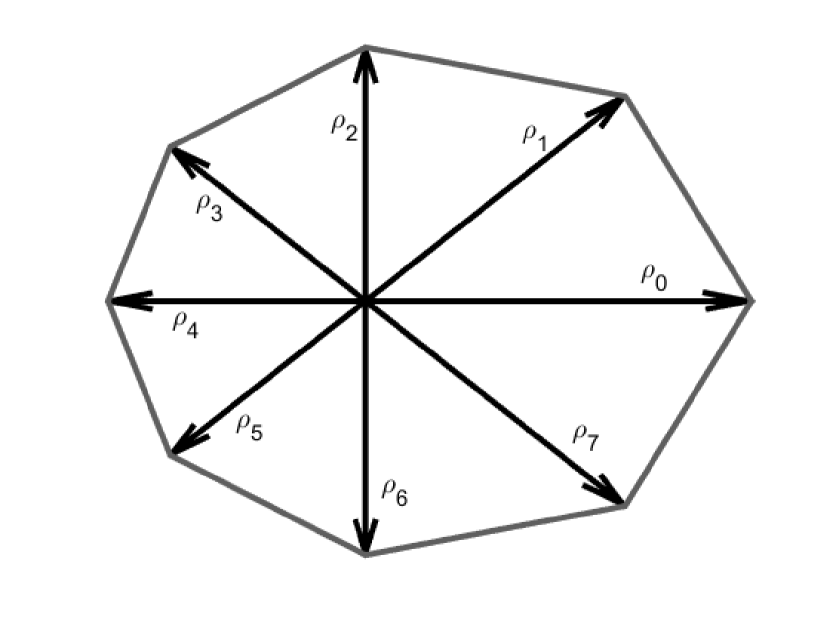

Polar representation of the contours reduce the degrees of freedom for each contour point such that the contour can only evolve radially. Each polar contour is sampled at certain angles, as shown in Fig. 3 as a contour with points.

A major shortcoming in existing AC algorithms is that they define similar energy terms for all contour points, despite the fact that intensity and shape vary across the region of interest. To overcome this problem, the proposed algorithm weights the energy terms locally. For example, if part of the IJV contour is obscured by shadow then the algorithm assigns smaller weights to the external energy of the points in the shadowed region such that increased emphasis is on the internal energy terms. Similarly, if a part of the contour has a sharp curvature, the algorithm gives a smaller weight to the curvature energy term for points in areas with sharp edges. These small, non-zero weights enable the contour points to have larger curvatures while still contributing to the total energy. Furthermore, regional variations in intensity are incorporated by subdividing the region of interest (ROI) into multiple sectors with each sector containing one contour point and values of and calculated locally as shown in Fig. (4).